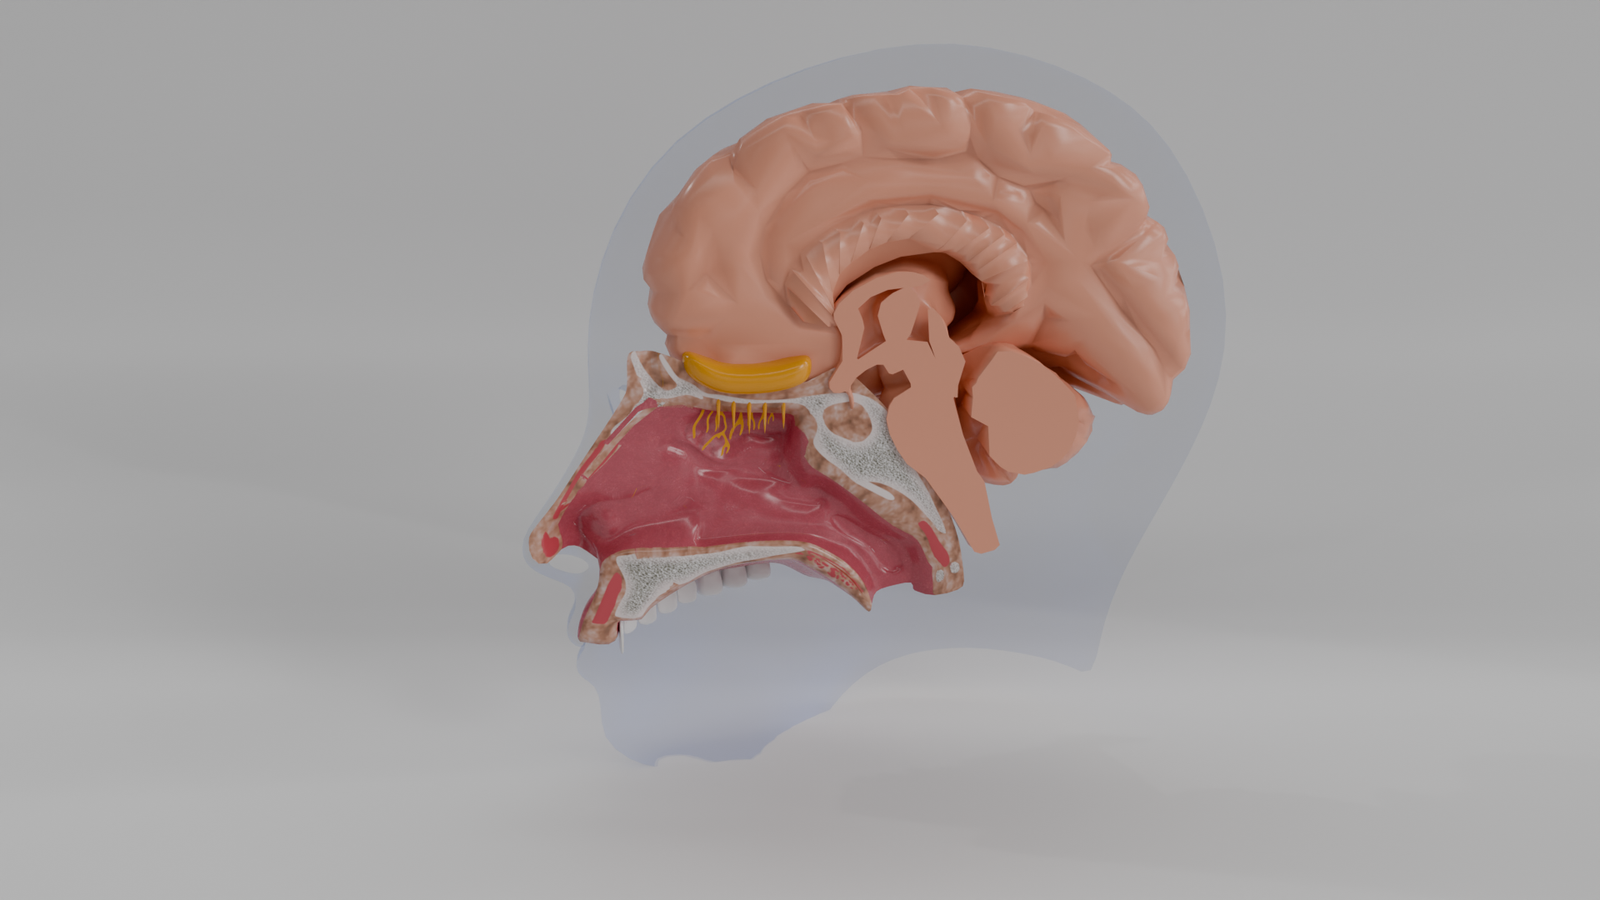

Olfato Humano

Modelo 3D educativo